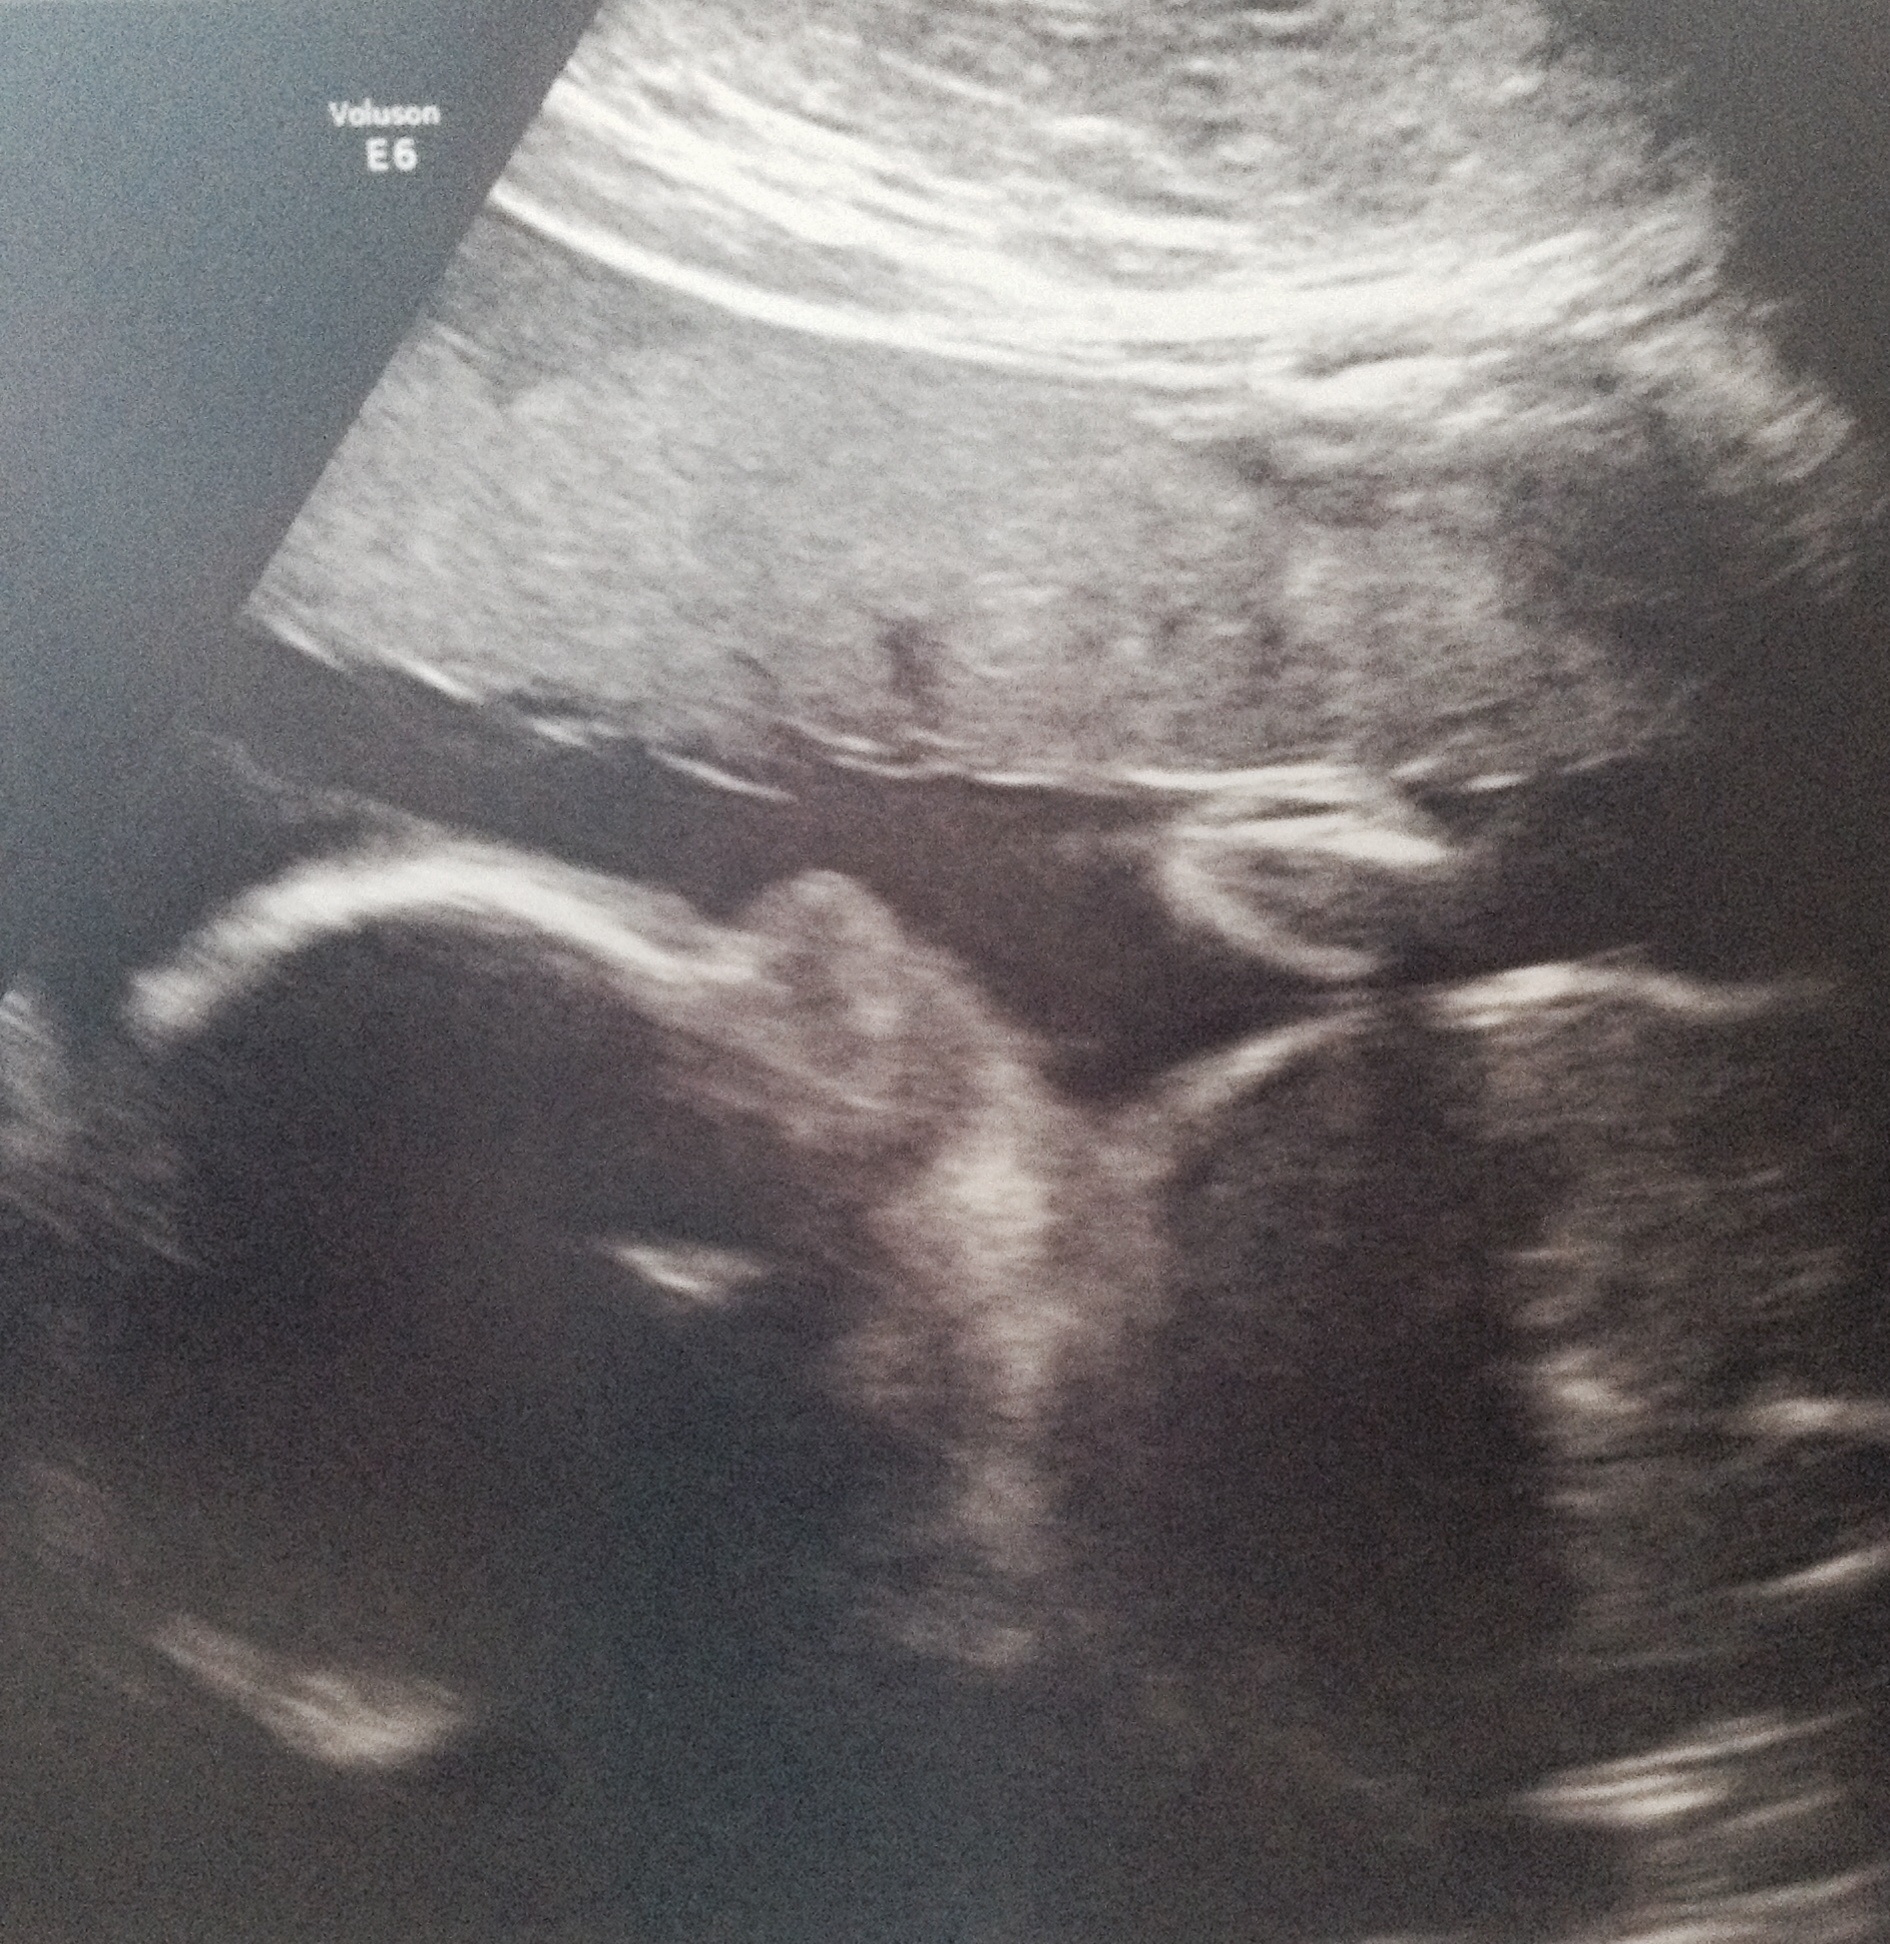

I cannot believe I made it to the 3rd trimester! Peyton has been moving a ton lately which is awesome.

Had an appt yesterday - she's measuring a little big according to the tech (60th percentile) & weighs approx 2lbs 11oz. Only 12 more weeks to go & SO much to do! :)